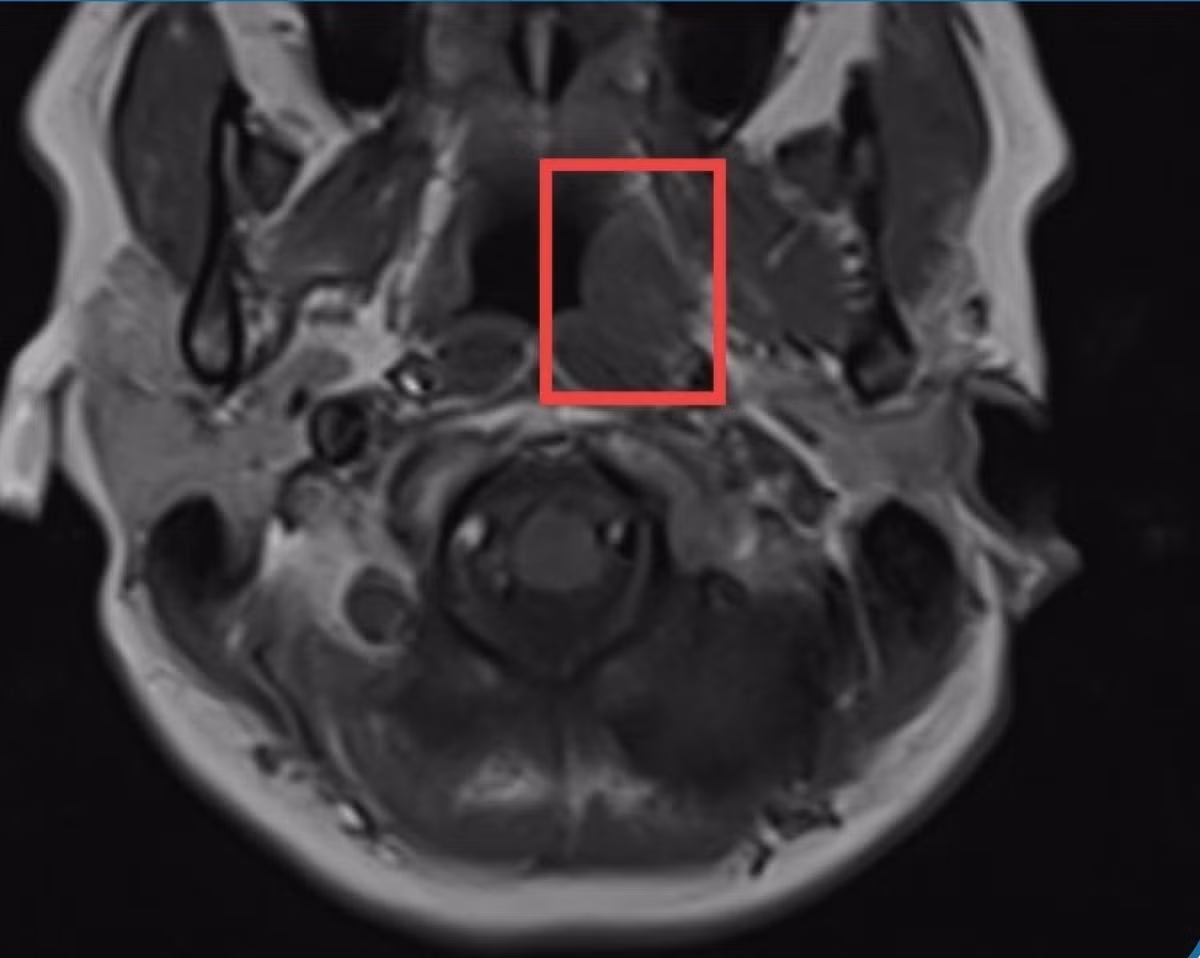

Ngày 31/7, bác sĩ Võ Bá Thạch, Trưởng khoa Liên chuyên khoa Bệnh viện đa khoa Xuyên Á Long An, cho biết qua thăm khám, nội soi mũi cho nữ bệnh nhân đã phát hiện khối u hố Rossemuler bên trái lan lên ngách sàng bướm trái, nghĩ nhiều đến ung thư vòm họng nên được chụp MRI để đối chiếu.

Kết quả ghi nhận khối u bất thường. Tiến hành sinh thiết, bác sĩ chẩn đoán bệnh nhân bị ung thư vòm họng.

Vị trí khối u trên hình ảnh chụp MRI sọ não. Ảnh: BVCC